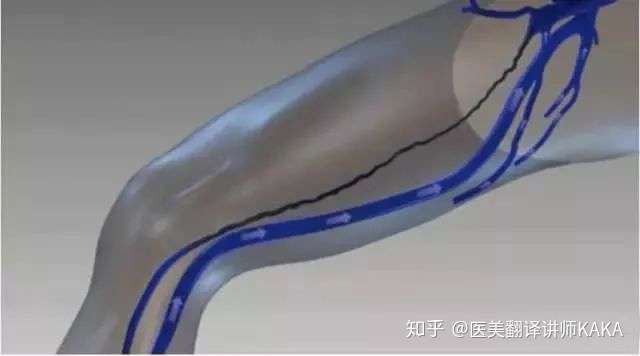

下肢静脉瘤分为以下四种 1伏在静脉 来自東京血管外科 Spectrum 微博

警惕 长在腿上的 蚯蚓 藏着致命危险 知乎

下肢静脉瘤

警惕 长在腿上的 蚯蚓 藏着致命危险 知乎